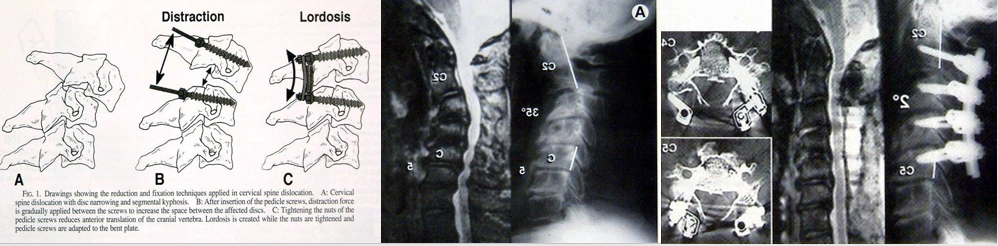

Abumi技术–进钉点在关节突的中点稍偏外,靠近上关节突的后缘,螺钉内聚30°至40 ° ,高速磨钻,直视下的进钉点。

• Abumi – 矫正颈椎后凸 + 减压, 枕颈融合

病例